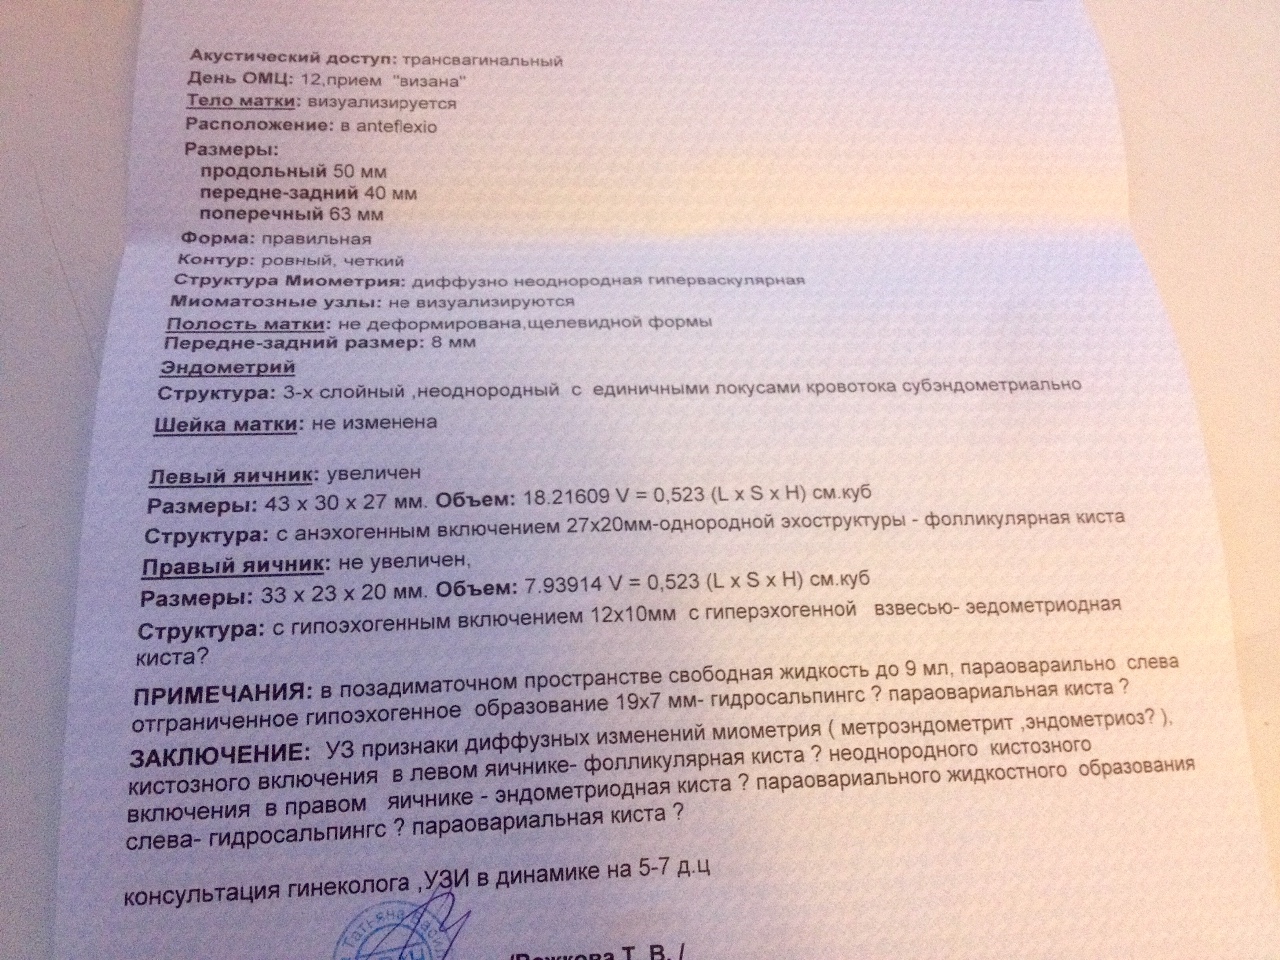

Гистологические изображения фолликулярной кисты яичника

Раздел: Лаборатория идей